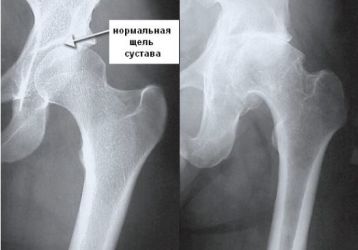

Какой врач лечит коксартроз тазобедренного сустава: от диагностики до операции

Какой врач лечит коксартроз тазобедренного сустава зависит от стадии заболевания. Терапевт, травматолог, флеболог, ревматолог.